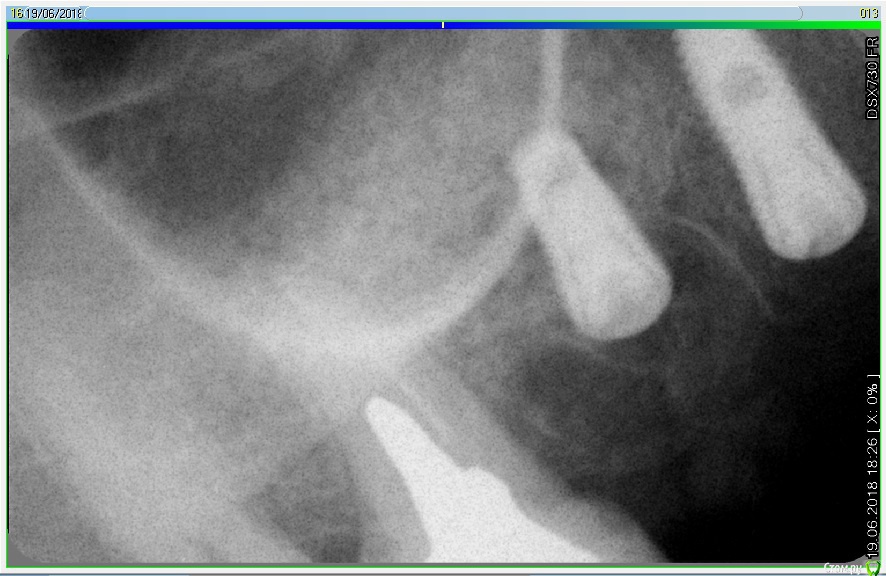

Лералена Опубликовано 14 октября, 2018 Автор Поделиться Опубликовано 14 октября, 2018 На двойном снимке, ситуация до установки мплантатов и после удаления. Ссылка на комментарий

Лералена Опубликовано 8 января, 2019 Автор Поделиться Опубликовано 8 января, 2019 (изменено) Подскажите пожалуйста, правильно ли установлены импланты? Картина такая, удалили 14 и 16 зубы, 15 давно нет, удалили 10 лет назад. Поставили импланты не понятно как, вроде как 15 и 16, как сказал врач. Самих имплантов уже нет, удалили на 8 сутки, прошло достаточно времени чтобы повторить операцию. Но, прежде хочется понять, стоит идти к этому врачу, зовет бесплатно устранить все, или все же не стоит рисковать и обратиться к другому. Диагноз после удаления имплантов звучал как Периапикальный абсцесс.Спасибо за ответ! Изменено 8 января, 2019 пользователем Лералена Ссылка на комментарий

Лералена Опубликовано 8 января, 2019 Автор Поделиться Опубликовано 8 января, 2019 (изменено) А вот и сами снимки, если конечно по ним можно что-то сказать. Изменено 8 января, 2019 пользователем Лералена Ссылка на комментарий